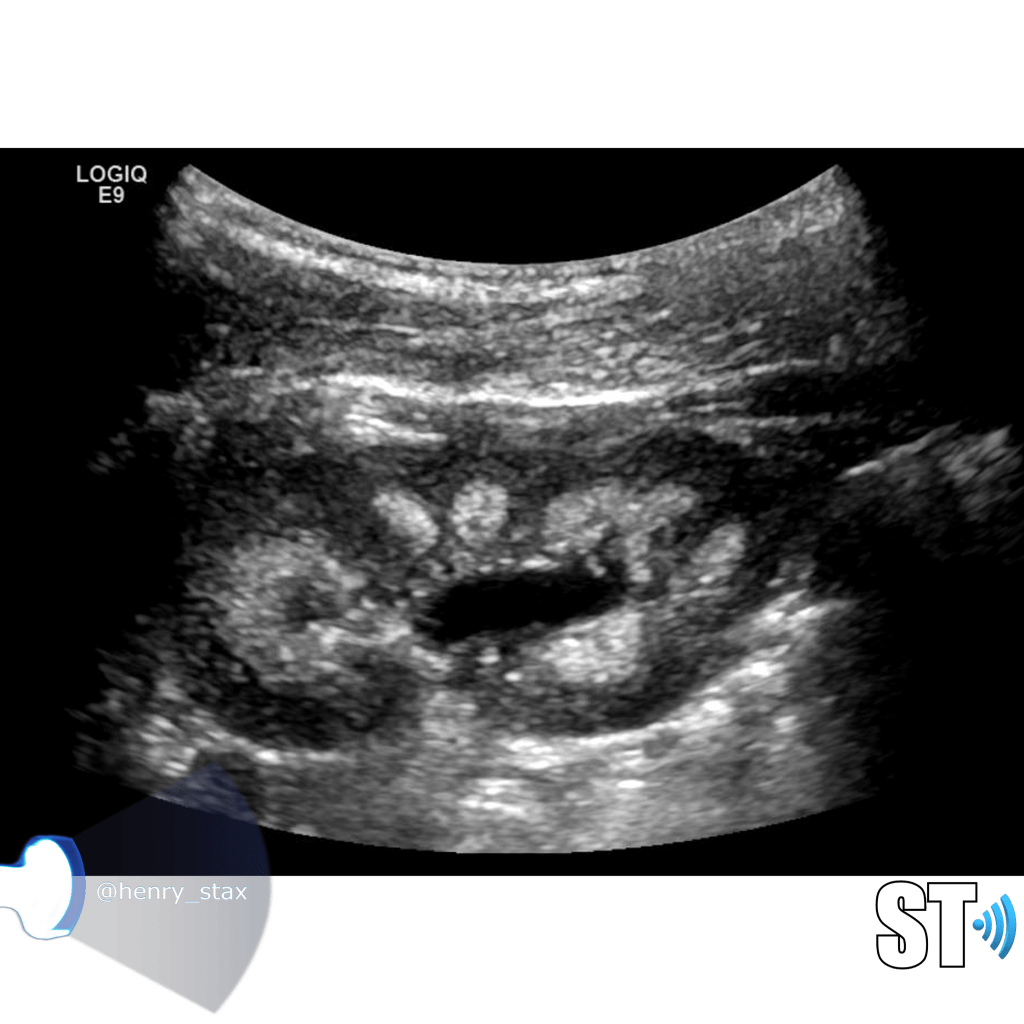

A simple way to grade hydronephrosis is by severity, mild to severe.

Mild

Pelvic fullness with no calyceal dilatation

Moderate

Greater expansion of the renal pelvis and involvement of the calyces

Severe

Further dilatation of the renal collecting system with cortical thinning

It’s good practice to always place color doppler on mild hydronephrosis or extra-renal pelves to distinguish a true fluid collection form a prominent renal vein.